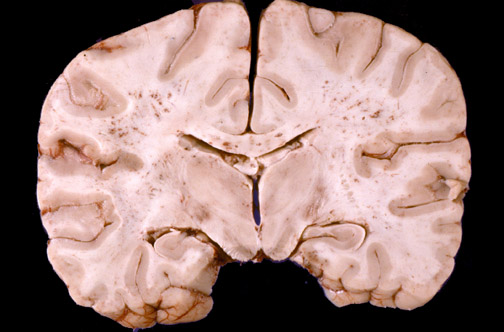

| From several days to a week following the event initiating fat embolism syndrome, there may be loss of consciousness from lesions evidenced by the "brain purpura" as shown here. Numerous petechial hemorrhages are produced by fat emboli to the brain, particularly in the white matter. Subsequent to this there can be brain edema with herniation. |